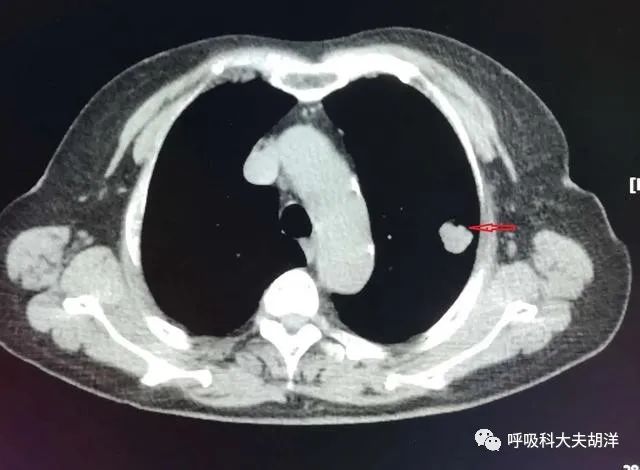

还是那句话,没有任何一种单一的特征可以直接判定结节的良恶性,像下图红箭头所指的这个结节,有明显的分叶,但最终证实是一个错构瘤,这是一种良性肿瘤,不做手术也是可以的,但由于有明显的分叶,而忽视了里面一些钙化成分,从而被当做肺癌开掉了。